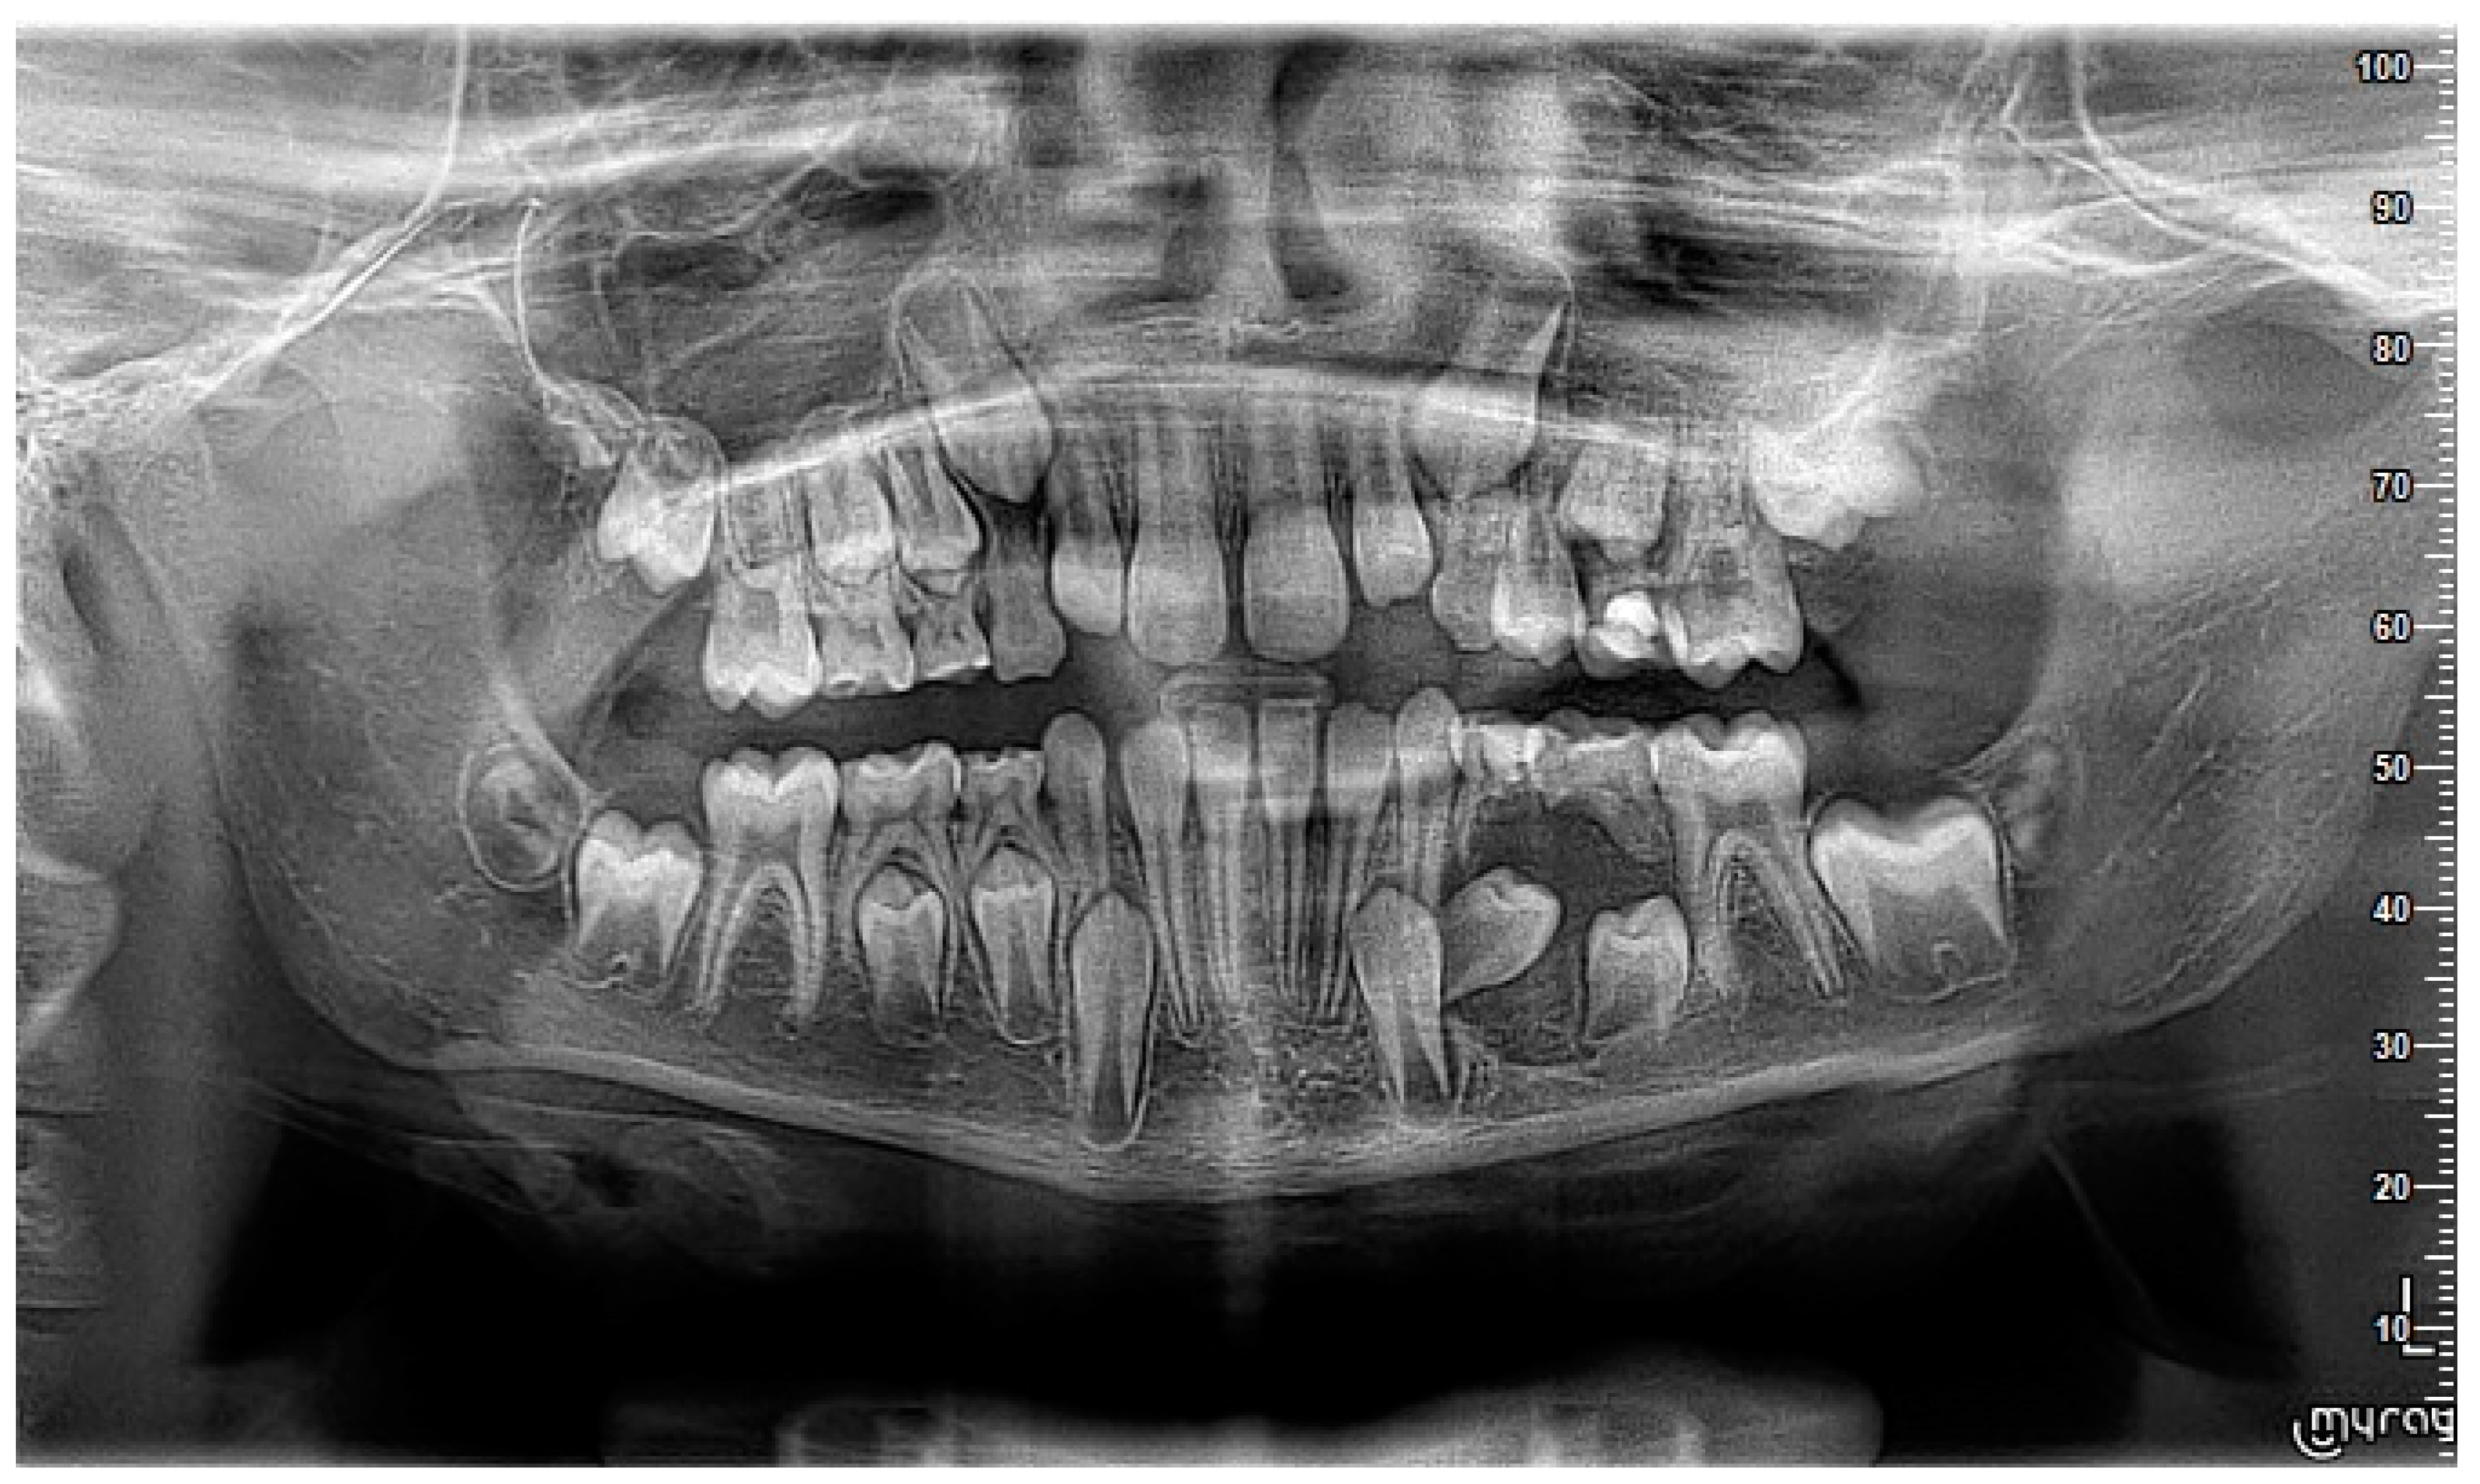

2. Case Report

3. Follow-Up and Outcomes